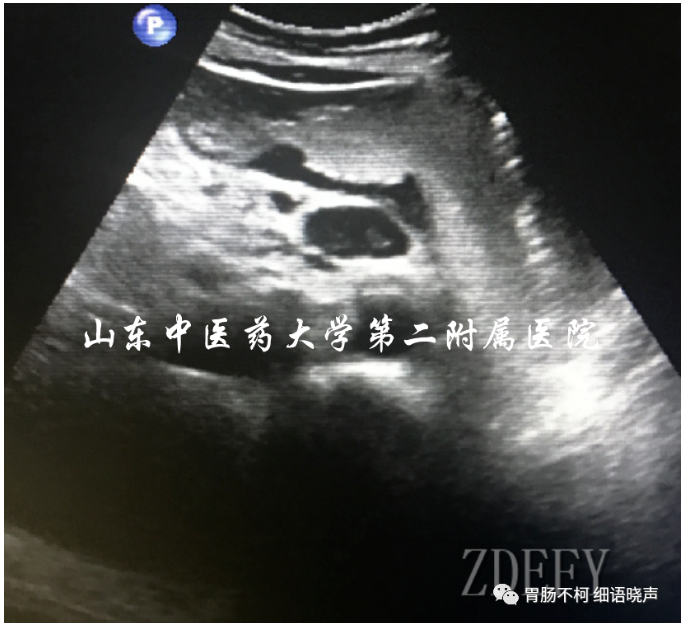

“土堆挖坑征”是恶性溃疡的征象。恶性溃疡发生的病理基础是肿瘤因生长过快,其中央肿瘤组织因血液供应不足导致缺血坏死,坏死组织脱落形成溃疡。所以,是宛若平地的胃壁新生物在先(“土堆”形成),坏死组织脱落溃疡形成在后(挖坑),故为“土堆挖坑征”。溃疡底部因坏死组织脱落所致不平整。典型病例如下: